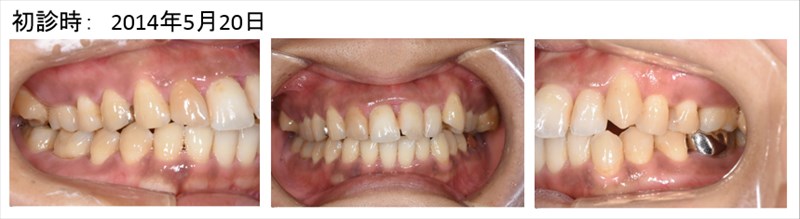

この症例の患者さまは前歯の腫れと膿を主訴にいらした患者さまです。

前歯の中央が腫れで赤みを帯びていますね、

6mmのポケットがありました。